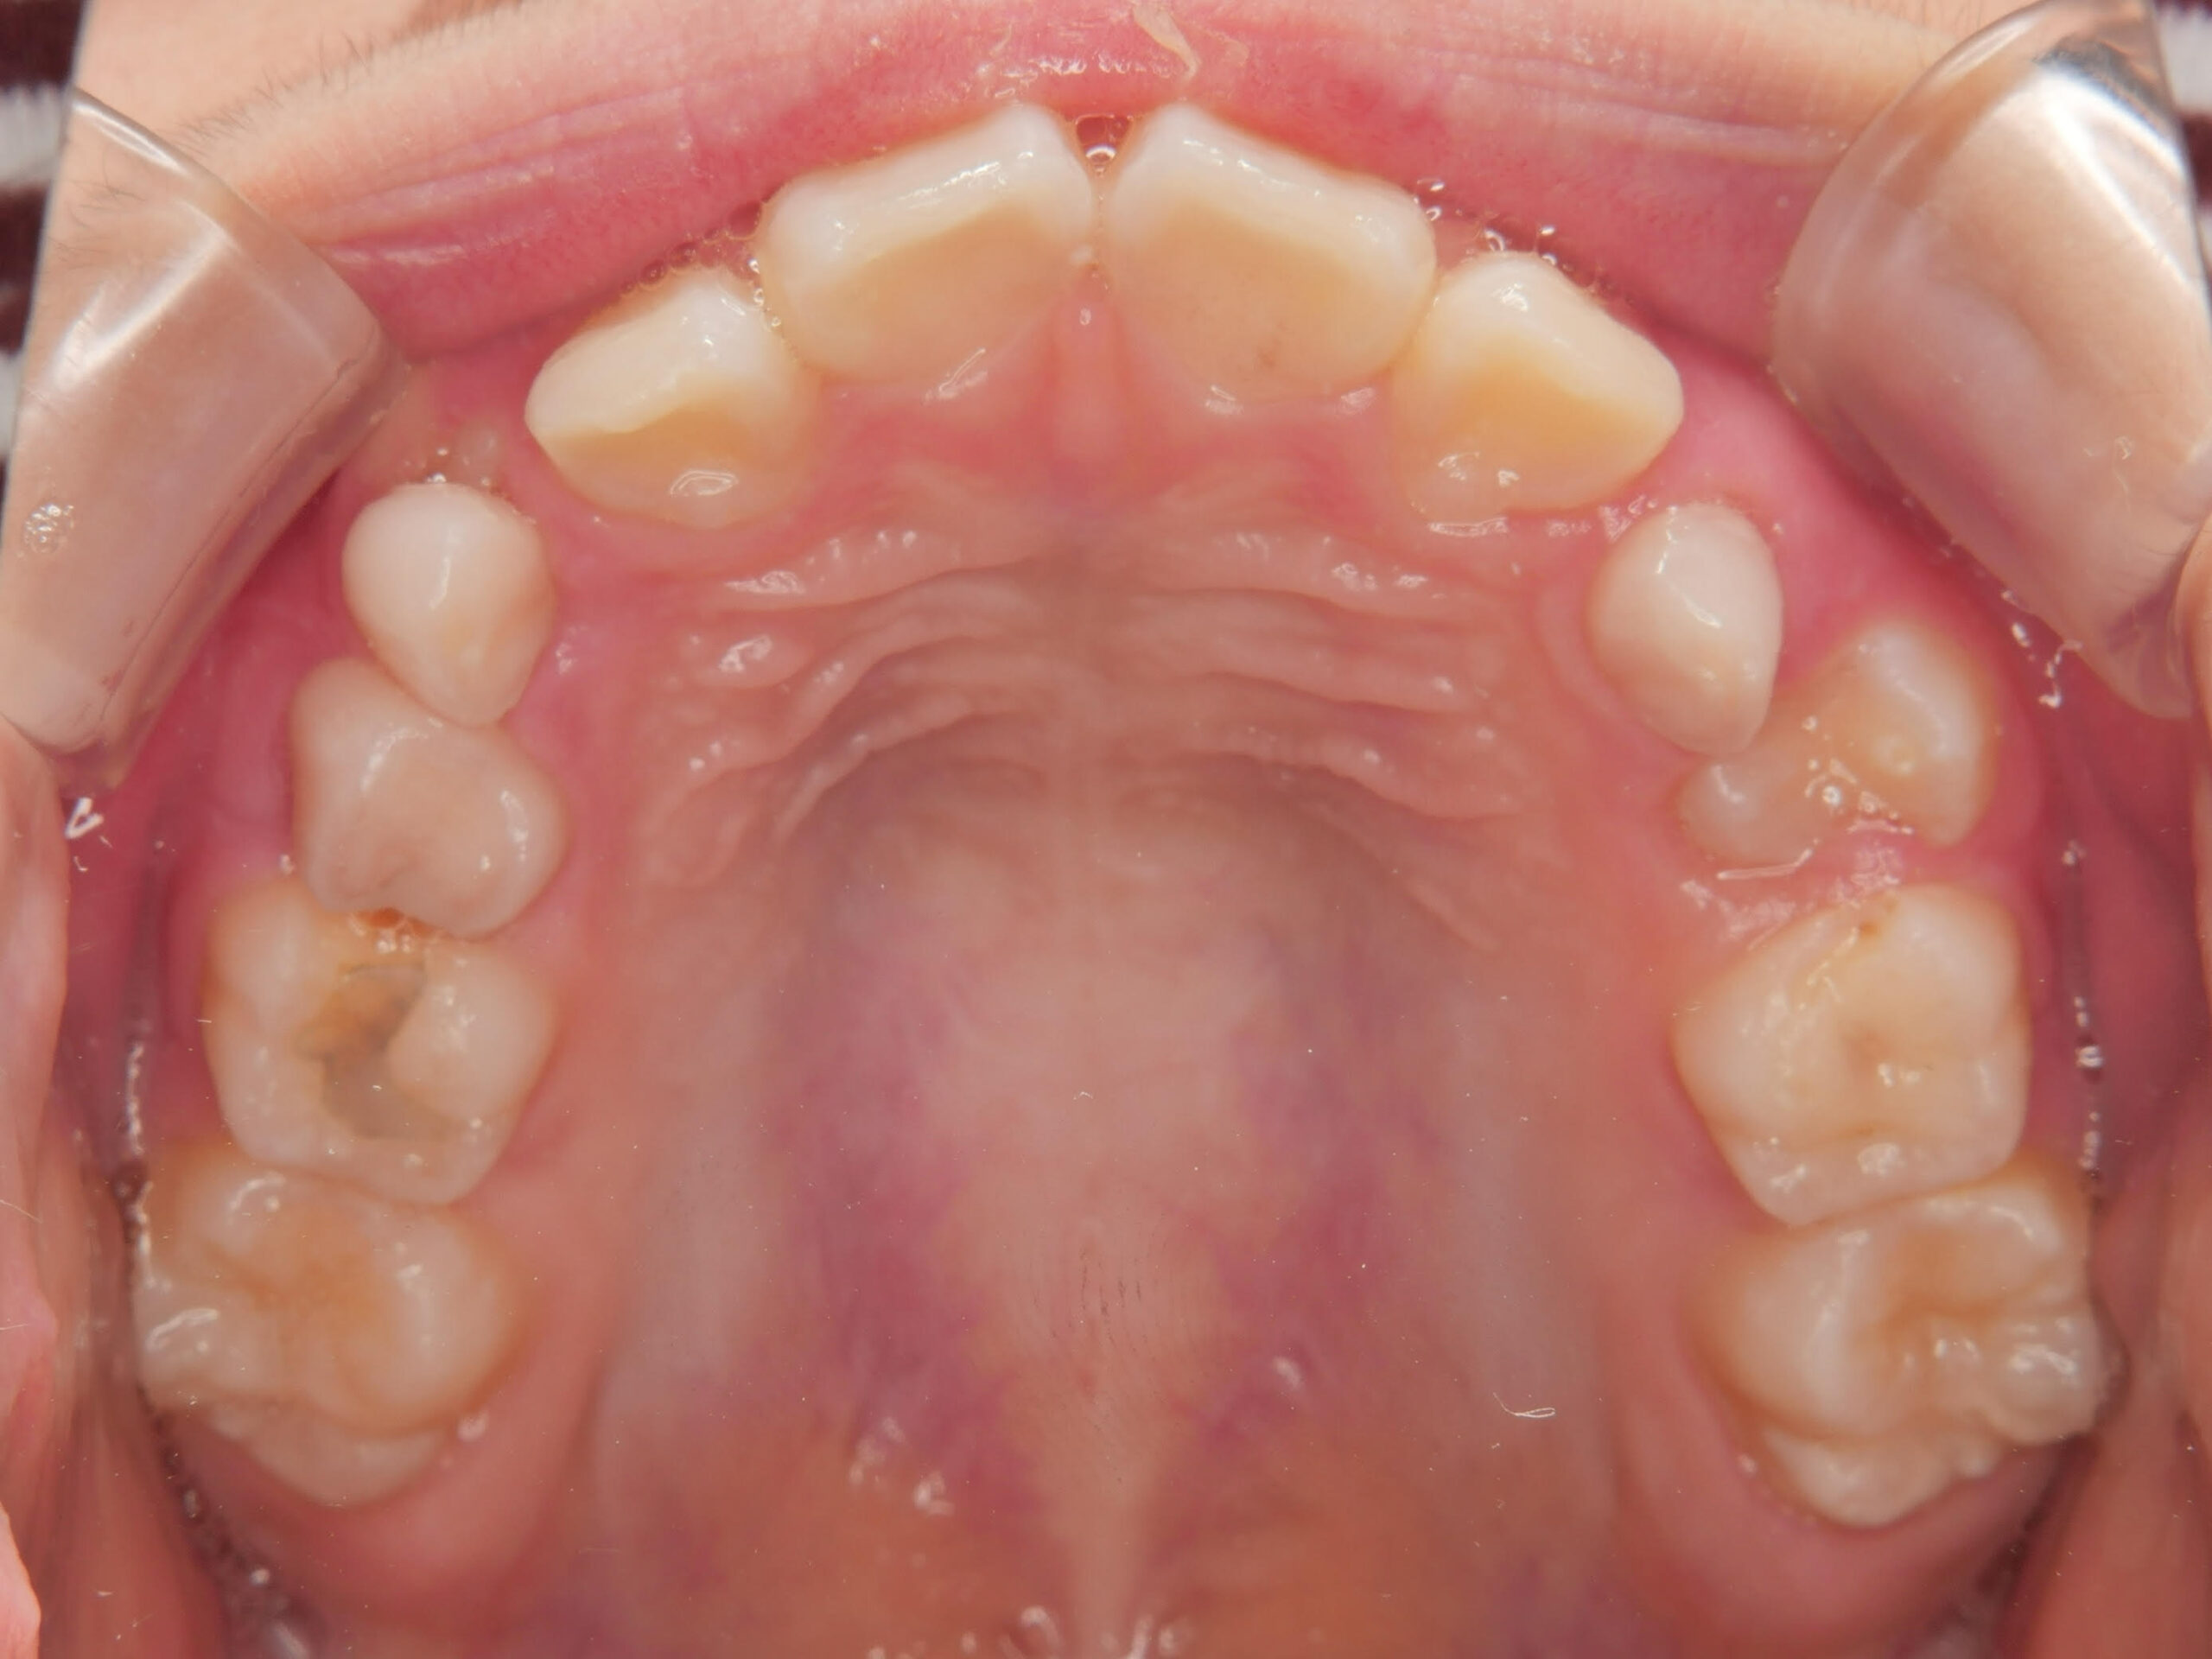

初診時の画像診断

上下の歯並びにガタガタがあります。

左の前から3番目の歯の噛み合わせが上下反対に噛んでいます。

その影響で上下の前歯の真ん中のラインが右にずれています。

1つ目は、上下ともに少しガタガタがあること。

2つ目は、噛んだ時に上下の前歯の真ん中のラインが少しズレていること。

3つ目は、左側の一部だけ上下が逆に噛んでいる(交叉咬合)ところがあることです。